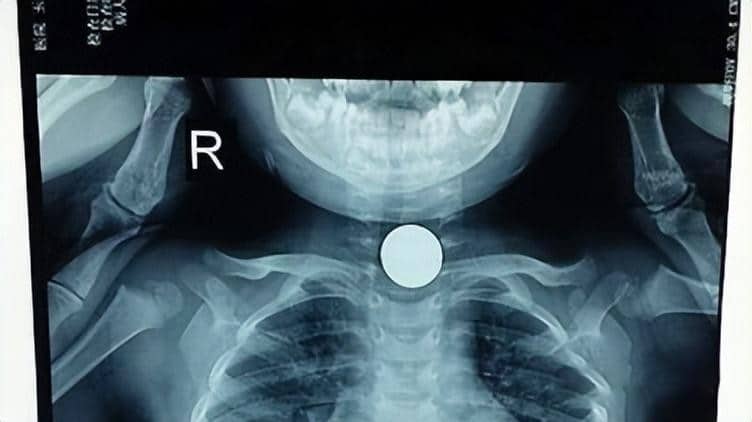

เมื่อวันที่ 28 ม.ค. 67 เว็บไซต์ Phunuphaplua รายงานข่าวสลด กรณีเด็กหญิงวัย 3 ขวบในเมืองหางโจว (Hangzhou) ประเทศจีน เสียชีวิตจากการสำลักลูกอมในทางเดินหายใจ โดยพ่อแม่ไม่ทันสังเกต เหตุการณ์นี้สร้างความตื่นตระหนกในโซเชียลมีเดียจีนเป็นอย่างมาก

ในขณะเกิดเหตุ แม่ของเด็กกำลังทำอาหารอยู่ในครัว ส่วนพ่อที่ควรจะดูแลลูกอย่างใกล้ชิดกลับเผลอหลับไปเพียงไม่กี่นาที จู่ ๆ ลูกน้อยเกิดอาการหน้าแดง หายใจถี่ขึ้น จากนั้นอาเจียนออกมาอย่างรุนแรงและไม่หยุด ทำให้พ่อและแม่รีบพาไปโรงพยาบาลไปโดยด่วน แต่สุดท้ายไม่ทันการณ์ แพทย์และพยาบาลช่วยชีวิตลูกน้อยไม่ทัน ทำเอาคนเป็นแม่ใจสลาย ตบตีสามีด้วยความโกรธเพราะไม่ดูแลลูกให้ดี